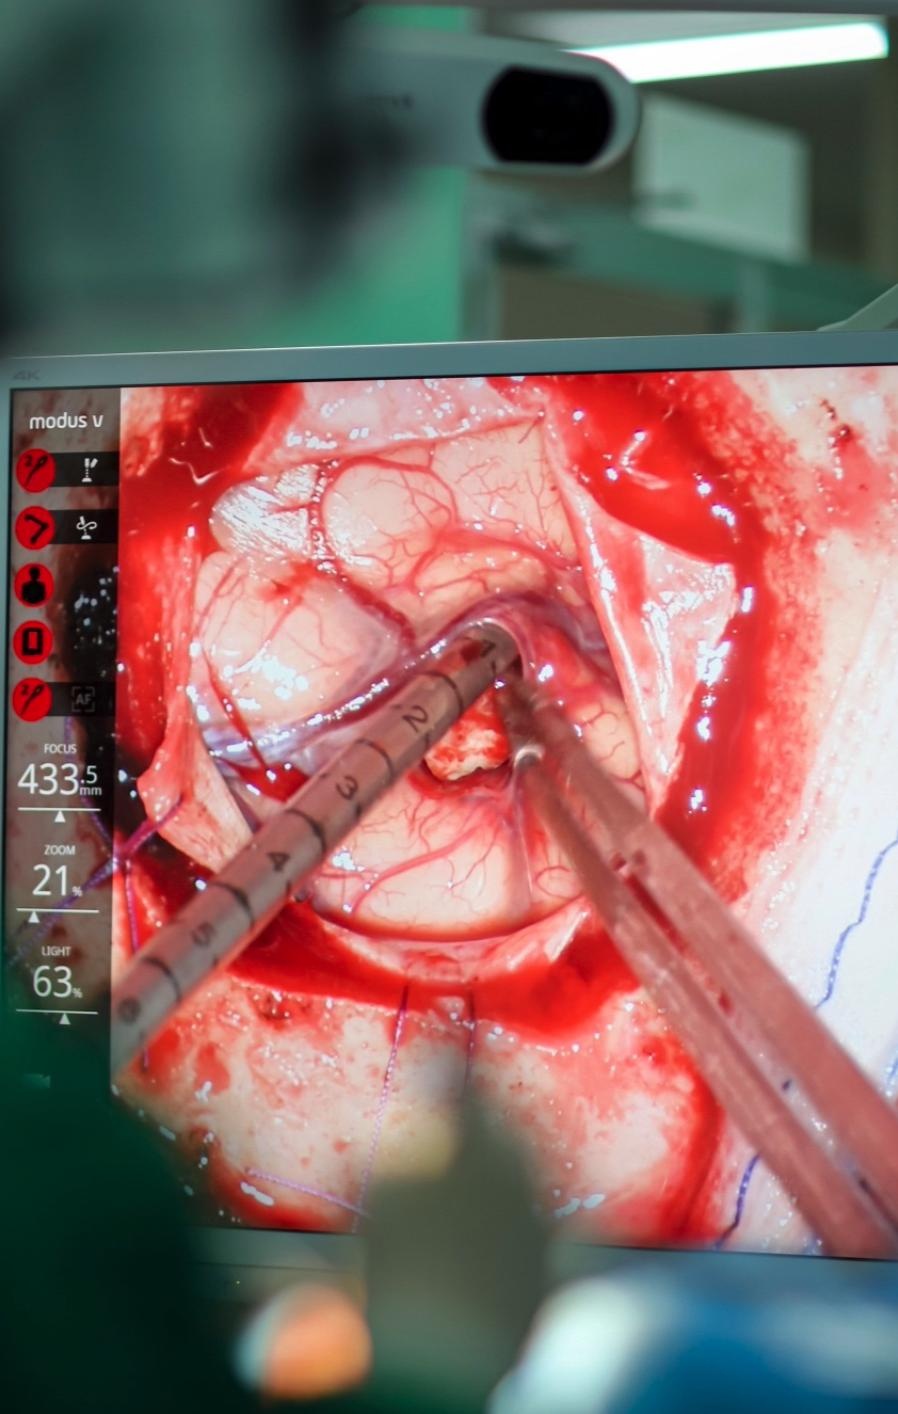

| Bệnh nhân được che chắn lại toàn bộ vùng mắt trở xuống. Bác sĩ phẫu thuật chỉ nhìn thấy và thao tác mổ với vùng sọ trong phẫu trường với bán kính khoảng 4 cm. Một đường dao được rạch cẩn thận trên vùng da đầu. Hộp sọ được mở ra. Phẫu thuật viên tiếp tục rạch thêm đường dao để mở lớp màng não. |

| Kỹ thuật viên bên ngoài điều chỉnh độ phóng đại 50% trên màn hình từ “bụng robot”. Lúc này, phẫu thuật viên có thể nhìn thấy rõ từng mao mạch. Bác sĩ Sĩ cho biết trước đó, bác sĩ phải được đào tạo liên tục và thực hành trên xác nhiều lần mới có thể tiến hành thuần thục khả năng “tay phẫu thuật một nơi, mắt nhìn màn hình nơi khác ”. |

| Màn hình bên trái là hình ảnh mô phỏng phim MRI có vị trí khối u. Phần màu cam là khối u trong não. Phần được tô nhiều màu sắc là các bó sợi thần kinh. Nếu phẫu thuật viên can thiệp ngoài vùng khối u, chạm vào bó sợi thần kinh này, robot sẽ lập tức phát tín hiệu cảnh báo. |

| Tay trái bác sĩ cầm ống hút gắn bút định vị có đường kính 3 mm. Trong suốt cuộc mổ, những “đôi mắt định vị” này sẽ xác định ống hút đang ở vị trí nào của khối u, từ đó giúp người mổ điều chỉnh đường đi đúng hướng. Tay phải bác sĩ cầm dụng cụ mổ tích hợp thực hiện gắp, cắt khối u và cầm máu. Nếu u nhỏ, bác sĩ sẽ nhanh chóng gắp ra ngoài. Nếu kích thước to, khối u được cắt nhỏ và gắp ra lần lượt. |